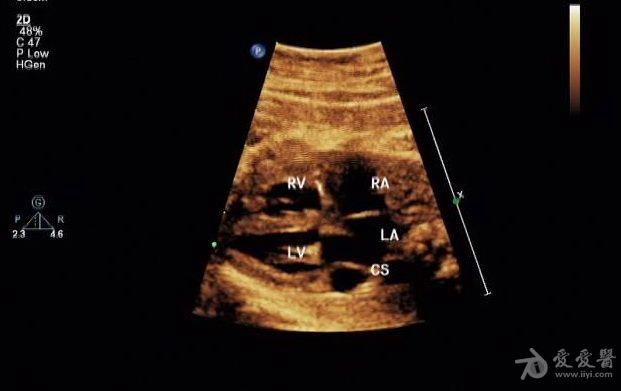

胎儿永存上腔静脉

冠状静脉窦增宽约

0.8 cm

,心底部三血管切面显示肺动脉左侧管腔样结构,频谱显示为静脉频谱。